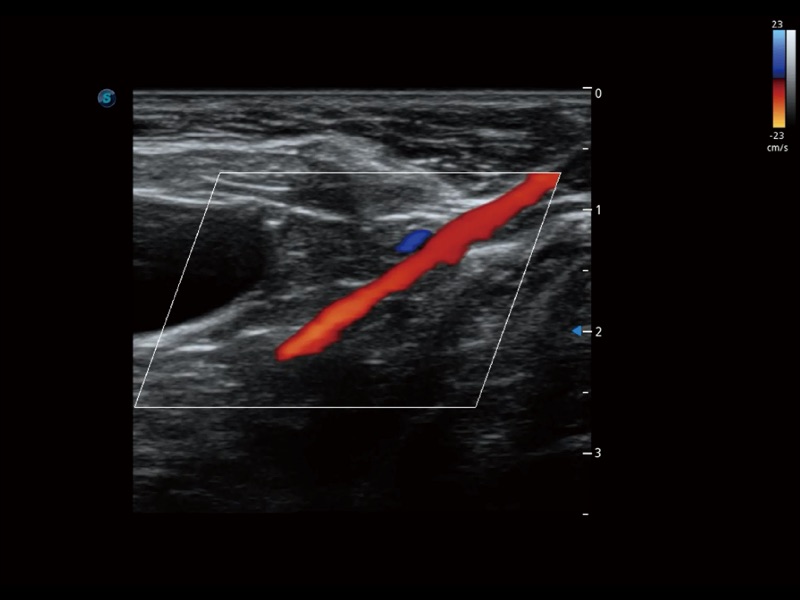

通过创新的 Matrix E自适应滤波器和超长时间域算法,极大提升超低速微细血流的检出能力,同时更精准地滤除软组织和噪声信号,为兽用医生提供以往无法通过常规血流获得的疾病诊断信息。

通过色彩血流和实时宽景相结合,可观察到完整的静脉或动脉的血流,方便医生检查。实时扫查过程中,如有任何操作失误也可以很容易地进行回扫擦除,而不会中断扫查。